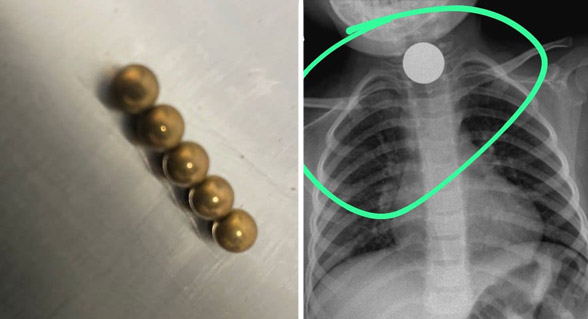

نقل 4 أطفال لمستشفى أشدود بعد ابتلاعهم قطع نقدية وأجواء ألعاب مغناطيسية